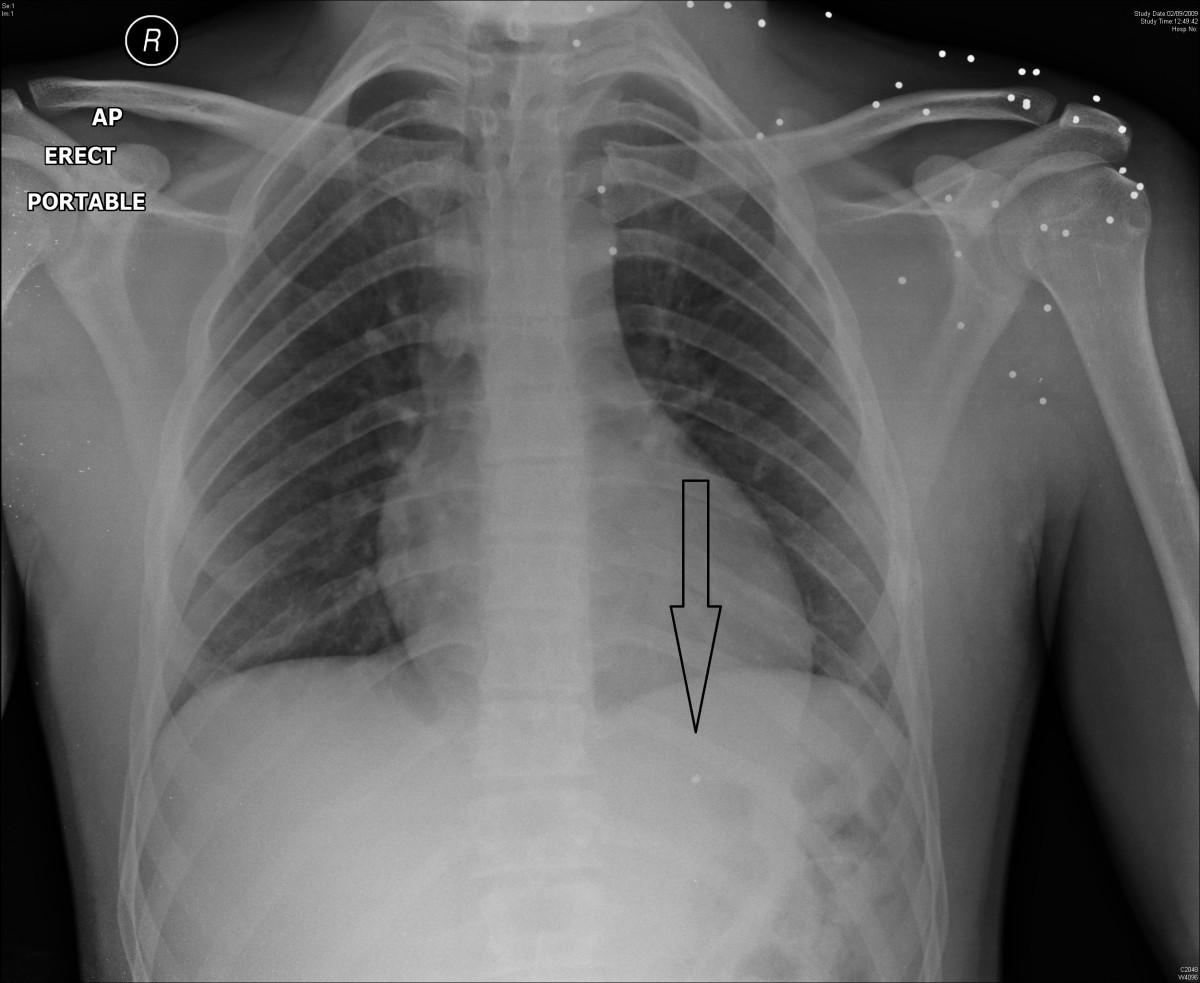

Gunshot bullet embolus with pellet migration from the left brachiocephalic vein to the right

From sjtrem.biomedcentral.com

Gunshot bullet embolus with pellet migration from the left brachiocephalic vein to the right What Does A Bb Gun Shot Look Like Being shot by a bb gun can be painful and may cause a stinging. It was selected for w.f. — what does it feel like to get shot with a bb gun? A bb gun typically resembles a real firearm, but it is smaller in size and shoots small. — bb guns shoot round projectiles, while pellet guns. What Does A Bb Gun Shot Look Like.